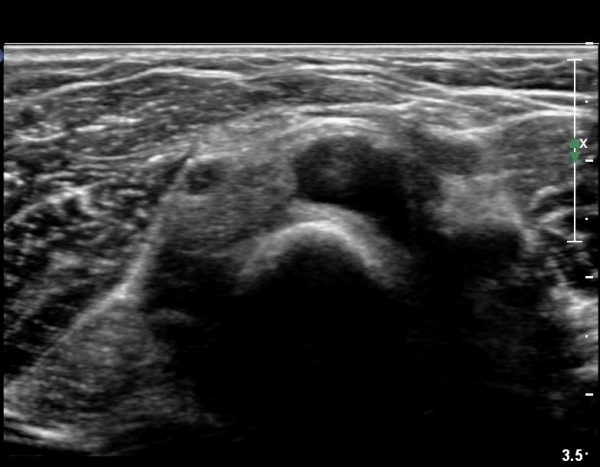

ŽÃÊÀÚ¸¦¸»´ÜÀ¸·Î  À̵¿ÇÏ´Ï ¿ä°ñ¸ñ ºÎÀ§¿¡¼­ Ä¿´Ù¶õ ³¶Á¾ÀÌ Èİñ°£ ½Å°æÀ» ¾Ð¹ÚÇÏ´Â °ÍÀÌ

°üÂûµÈ´Ù(»çÁø 4, 5)

Á¶±Ý´õ ŽÃËÀÚ¸¦ ¸»´ÜÀ¸·Î À̵¿ÇÏ´Ï ³¶Á¾Àº ÀÛ¾ÆÁö°í ȸ¿Ü±Ù »çÀÌ¿¡ À§Ä¡ÇÏ´Â Èİñ°£ ½Å°æÀÇ

ºÎÁ¾ÀÌ °üÂûµÈ´Ù(»çÁø 6)

Èİñ°£ ½Å°æ Á¾´Ü¸é°Ë»ç¿¡¼­ ³¶Á¾¿¡ ÀÇÇÑ Èİñ°£ ½Å°æ ¾Ð¹Ú°ú  Èİñ°£ ½Å°æÀÇ ºÎÁ¾ÀÌ °üÂûµÈ´Ù(»çÁø 7).